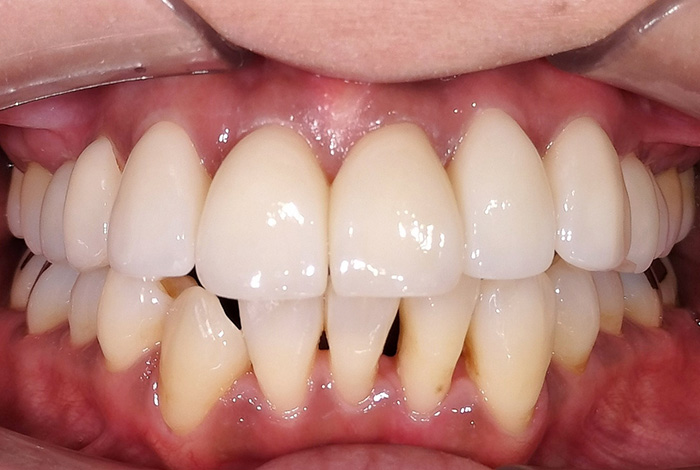

前歯の変色と摩耗による長さの不ぞろいを改善した審美治療症例

Before

After

【術前】:前歯の変色と歯ぎしりによる摩耗により、長さの不ぞろいがみられました。

【術後】:ジルコニアプレミアムクラウンで色調と形態を整え、自然感のある口元に改善しました。